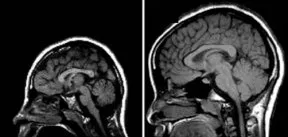

If a human brain and a mouse brain were sitting next to each other, the first thing you would notice is the difference in size. The second most obvious difference is that folds and furrows mark the surface of the human brain, while the surface of the mouse brain is smooth. The wrinkled portion of the human brain is the cerebral cortex, the multilayer region responsible for making sense of all the information streaming into a person’s head. In people, nonhuman primates, and other mammals with relatively large brains, the cerebral cortex’s convolutions permit its large surface area to cram inside the skull.

In the July 19 Science, Walsh and his colleague Anjen Chenn, now at Northwestern University School of Medicine in Chicago, described genetically engineered mice that develop cerebral cortexes with greatly increased surface area, so much so that the mouse brains have a more humanlike, wrinkled appearance. “It looks as if these wrinkles don’t require any special genetic tricks. It seems to be a passive response to having a brain that’s bigger than your head,” says Walsh.